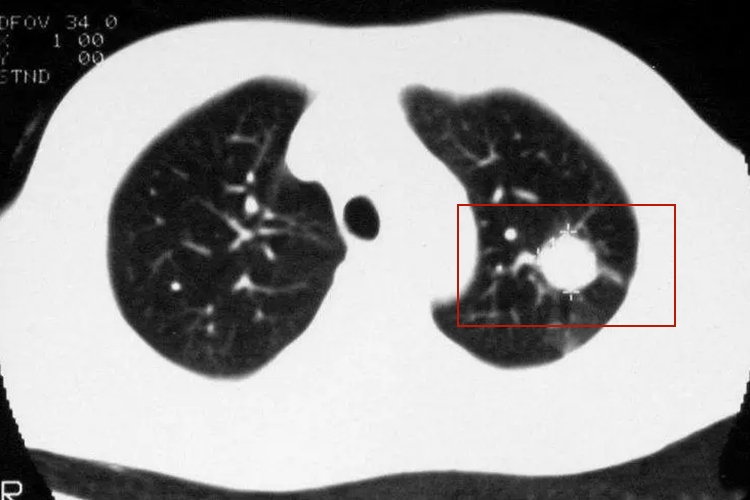

继发性肺结核:具体表现多样,如斑片影、空洞、结核球等。影像学可出现局限性斑片影,见于两肺上叶尖段、后段和下叶背段,还可有肺段或肺叶大片致密性实变,其内可见一个或多个空洞,为虫蚀样空洞,边缘模糊。结核球为圆形椭圆形影,大小0.5-4cm不等,多为2-3cm,边缘清晰,轮廓光滑。